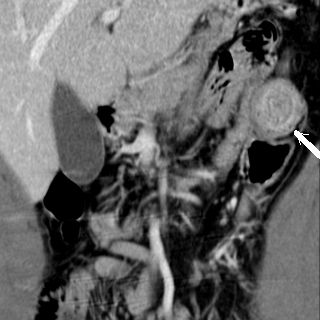

Image TDM en coupe

sagitale : Occlusion de l'intestin aigue avec

signe de bec de oiseaux ( fleche rouge ) et

dilatation intestinale en amont et signe de feces (

retention de feces au niveau de l'intestin sus -lesionelle |

Image TDM en coupe axiale :

Signe de feces' c'est la retention de fesce dans la

portion sus -lesionelle de l'intestin ( fleche

blanche ) . |